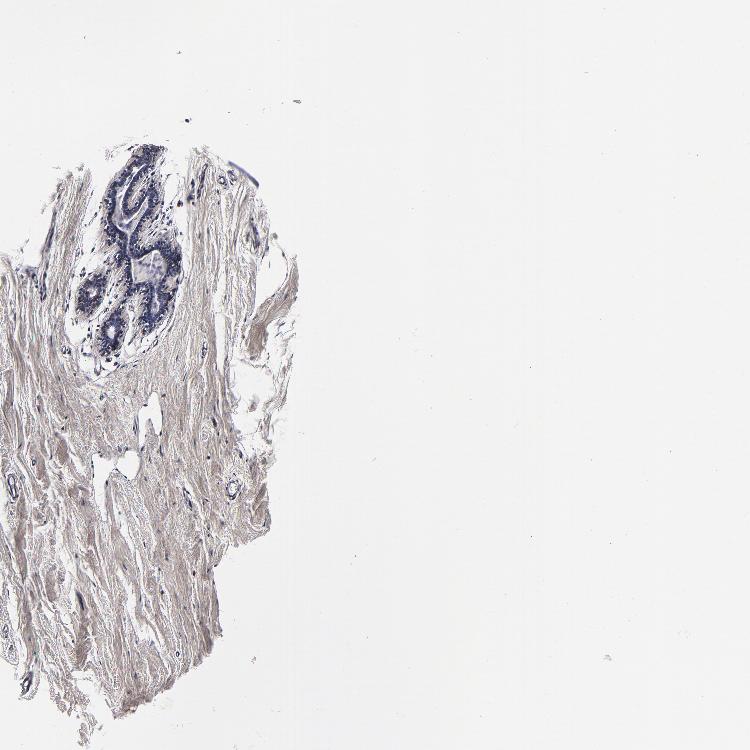

BREAST - Antibody stainingi

Antibody staining in the annotated cell types in the current human tissue is reported as not detected, low, medium, or high, based on conventional immunohistochemistry profiling in selected tissues. This score is based on the combination of the staining intensity and fraction of stained cells.

Each image is clickable and will lead to virtual microscopy that enables deeper exploration of all samples and also displays staining intensity scores, fraction scores and subcellular localization as well as patient and tissue information for each sample.

Antibody HPA040390Antibody CAB002611

Adipocytes MediumNot detected

Glandular cells MediumNot detected

Myoepithelial cells HighNot detected